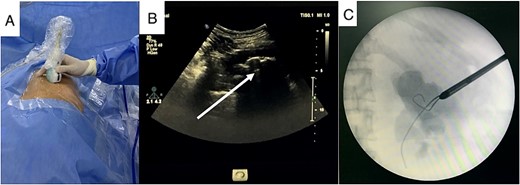

Baseline preoperative laboratory tests were normal. A lateral flank position mini PCNL was performed using combined US and flouroscopy guidance for renal puncture (Fig. 4A). After 35 min of lithotripsy, the stone burden was successfully removed, and the patient was discharged after 3 days without any complications. He declined treatment for his lumbar bulge after considering the risks associated with another operation.

Real-time US guide for renal puncture (A), mini PCNL with lateral position (B), and nephrostomy after completing stone clearance (C).